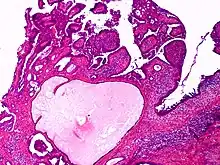

Apocrine gland carcinoma

Apocrine gland carcinoma, papillary type

Apocrine gland carcinoma is a cutaneous condition characterized by skin lesions which form in the axilla or anogenital regions.[1]:670